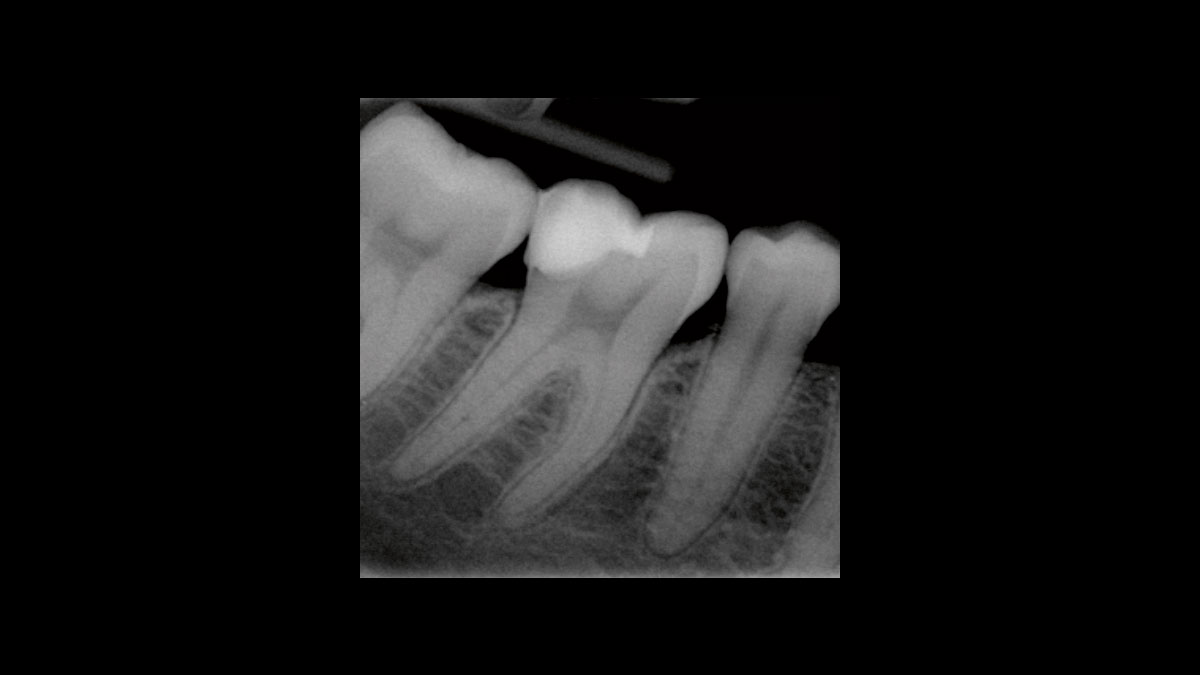

Endodoncia

Las siguientes aplicaciones se presentan en los videos y las imágenes:

• Reducción de bacterias en procedimientos endodónticos

• Reducción de gérmenes de la gangrena

Reducción de bacterias en procedimientos endodónticos